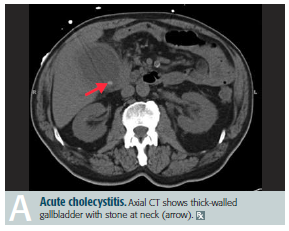

Cholecystitis